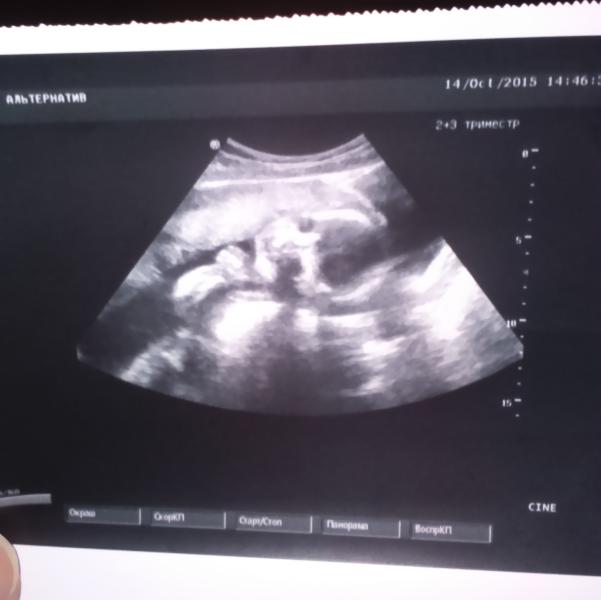

Мальчик мой, хочу уже поскорее его обнять)))